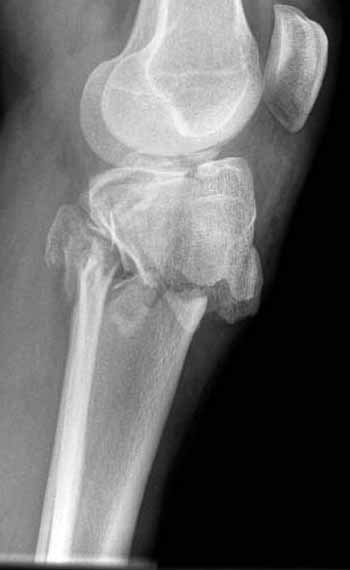

"участок некроза кожных покровов (см. фото), поэтому латеральная мыщелковая пластина не подойдет, а медиальных пластин у фирм-производителей нет. Пациент может приобрести современный имплант, но какой?"

Как понял, аппарат Илизарова не рассматривается предпочтительным для фиксации методом, хотя на фоне отека было бы идеальным для данного перелома. Для пластины требуется идеальная кожа, иначе наличие “суперсовременных имплантов” не поможет, и могут развиться серьезные осложнения.

В основном пластины рассчитаны на латеральную поверхность, потому что с латеральной стороны больше мягкотканая подушка, а также через латеральную колонну проходит ось конечности, что немаловажно в удержании оси от деформации.

Для изолированных переломов медиального тибиал плато, фиксацию можно провести “медиальной пластиной”. Некоторые компании, например Smith & Nephew делают медиальные и медиально-задние пластины, но они мягкие, и легко можно создать нужный контур. Жесткость создается за счет фиксации жесткими пластинами, например экстра артикулярной пластиной для дистального плеча от Synthes. Медиальный доступ тоже не из легких, надо работать между pes and medial gastroc.

Если у вас, кроме пластины, нет другого альтернативного варианта, тогда, учитывая мягкотканые проблемы с наружной стороны, я бы рекомендовал операцию делать в два этапа. Преимущества, сперва репозиция и фиксация перелома с медиальной стороны, а затем, после улучшения состояния мягких тканей, зафиксировать с латеральной стороны. Современные пластины имеют латеральный Jig для перкутанных мини доступов.

В приложении этапы фиксации Both Column Fx и пластиной Synthes для плеча при переломе медиального мыщелка.